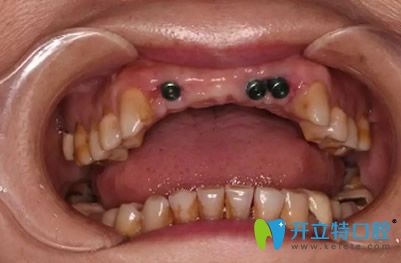

前牙缺失部位植入3顆種植體

植入種植體3個(gè)月后,檢查結(jié)果顯示,種植體與牙槽骨結(jié)合情況非常好,完全達(dá)到二期修復(fù)標(biāo)準(zhǔn)。為了實(shí)現(xiàn)好的美觀效果,孔醫(yī)生結(jié)合經(jīng)典的紅白美學(xué)標(biāo)準(zhǔn),按照牙齦、牙齒與面部的黃金比例,為路女士量身定制5顆全瓷修復(fù)體。

看看路女士在成都新橋口腔種牙前后效果對(duì)比圖:

成都新橋口腔種牙前后效果對(duì)比